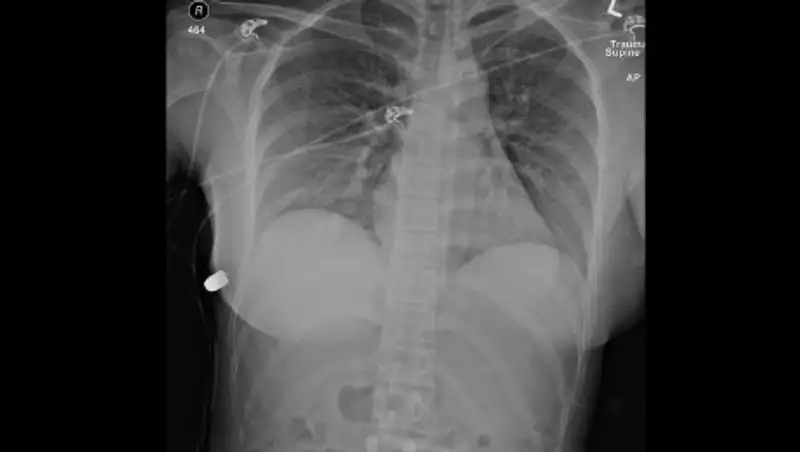

В Мангистау из грудной клетки 16-летнего подростка вытащили пулю от пневматического оружия, передает Zakon.kz.

Он сообщил, что 19 февраля в приемный покой областной детской больницы Мангистау был доставлен 16-летний подросток с пулевым ранением в грудную клетку. По словам сопровождающих, подросток по неосторожности получил ранение в одном из аттракционов (тир), находящемся в парке «Акбота».

После полного обследования 22 февраля врачи детской больницы провели сложнейшую операцию по извлечению инородного предмета из грудной клетки подростка.Азамат Сарсенбаев

По словам врачей, операция длилась примерно 40 минут.

Благодаря современному оборудованию эндоскопии в стенах детской больницы им (врачам. - Прим. ред.) удалось провести сложную операцию без существенных проблем. В противном случае, сетуют врачи, им бы пришлось вскрывать грудную клетку для того, чтобы вытащить инородное тело. В настоящий момент подросток чувствует себя хорошо и готовится к выписке.Азамат Сарсенбаев